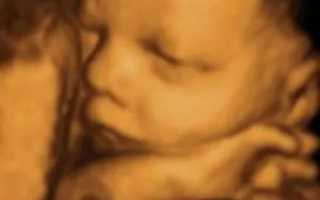

На 33 неделе беременности у ребенка появляются черты лица: уши, ноги, брови руки, ногти, начинают расти волосы. Все системы, за исключением: дыхательной, иммунной и нервной, практически сформированы. Вес малыша на 33 неделе в среднем 2 кг, а рост достигает 43-44 см. На этом сроке возможно подтекание околоплодных вод, что может свидетельствовать о маловодии.

Количество жидкости с течением беременности постоянно растет. В первом и втором триместре ребенок может еще сравнительно свободно перемещаться в матке, но уже к третьему триместру количество вод увеличивается, а с ними становится больше и сам ребенок, что приводит к сильной «тесноте».

При выраженном маловодии, в независимости от причин его возникновения, кроха страдает от гипоксии (нехватки кислорода), из-за этого он отстает во внутриутробном развитии. Ко всему этому малышу неудобно находиться в таком «гнёздышке», его шея часто искривлена, а кости лица и головы поддаются деформации из-за сдавливания их стенками матки.

Умеренное маловодие не так критично сказывается на состоянии здоровья плода: малыш слаб и отстаёт в наборе массы тела (наблюдается так называемая гипотрофия), его мышечный тонус снижен (возможно развитие кривошеи, косолапости), имеет место и слабовыраженная гипоксия плода.